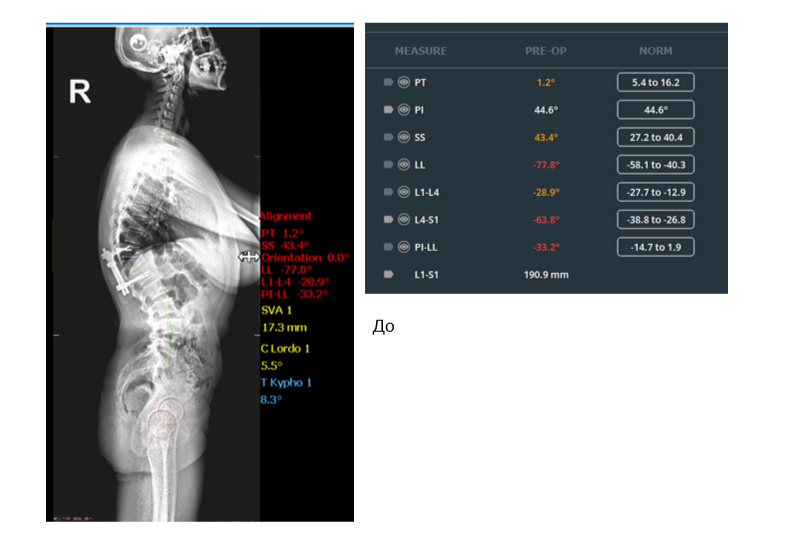

Именно с этим мы столкнулись у нашей пациентки. Через несколько лет в результате недостаточной стабильности фиксации произошел усталостный перелом металлоконструкции в результате циклических нагрузок в процессе жизнедеятельности пациентки. Сформировался грубый комбинированный (посттравматический+ постляминэктомический) грудопоясничный кифоз (50 градусов), сопровождающийся выраженными болями в спине. Почему так болит? Потому что деформация позвоночника приводит к дисбалансу туловища, включению компенсаторных механизмов и колоссальному перенапряжению мышц, обеспечивающих вертикальное положение тела в пространстве. Это молодая женщина трудоспособного возраста, состояние которой не позволяло вести полноценную жизнь, и помочь ей могла только хирургическая реконструкция позвоночника. Мы приняли решение о проведении трехэтапной операции в одну хирургическую сессию», — объясняет к.м.н., спинальный хирург, заместитель директора по лечебной работе Алексей Ластевский.

Задач у такой хирургии несколько: помимо чисто косметического эффекта, восстановление сагиттального профиля позвоночника позволяет выключить механизмы компенсации (поясничный гиперлордоз и грудной гипокифоз). Гармонизируя сагиттальный профиль позвоночника, специалисты приводят в соответствие параметры баланса: поясничный лордоз, грудной кифоз и разворот таза. Цель была достигнута — врачам удалось вернуть гармонию изгибов позвоночника. Колоссальное перенапряжение мышц уйдёт, а вместе с ним пациентку покинут и сильные мучительные боли.